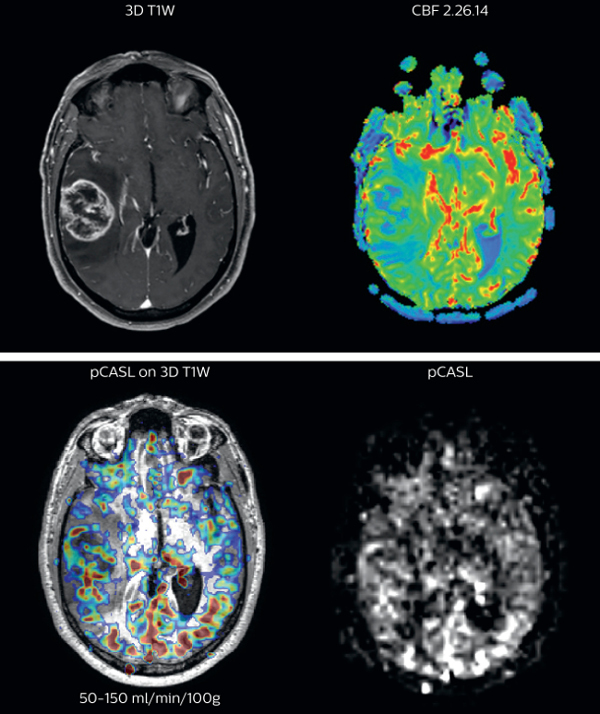

“In the cases in our study, pCASL was at least as representative as perfusion with contrast agent”

Brain perfusion imaging is typically performed using a contrast agent. However, pCASL allows visualization of brain perfusion and physiology without contrast agent injection. This fast sequence can be an alternative for perfusion imaging in patients who are contraindicated for use of gadolinium based contrast agents. “We have compared pCASL to T2*-weighted perfusion imaging with contrast agent in patientswith brain tumors”, says Dr. Nickerson. “In the cases included in our study, pCASL was at least as representative as perfusion with contrast agent. It’s a pretty big improvement if we’re avoiding giving gadolinium and we’re getting a quite equivalent dataset, that’s a pretty big improvement.”

pCASL broadly used in brain tumor patients

The pCASL method is now broadly used at UVM. “It’s a short sequence, and is ideal for use in patients where motion is a concern. pCASL is currently included in all our MRI exams for patients with a known tumor, either initial or post-operative and all follow-ups. Additionally, it can also be used when we examine for stroke. And of course, pCASL is an alternative allowing perfusion imaging in patients with compromised renal systems, for whom contrast agent is contraindicated.” “Furthermore, we image a fair number of pediatric tumors here and the repeatability of pCASL is a great benefit when scanning pediatric patients with brain tumors. If the patient moves during the acquisition of a DSC perfusion scan, we missed our shot. However, if a patient moves during pCASL, we can simply repeat the scan because there’s no contrast injection involved,” says Dr. Nickerson Richard Watts, PhD, brings forward another aspect. “Quantification with pCASL does not have the issue of selecting an arterial input function like with contrast-agent based scans. In the brain tumor studies that we’ve been running, we feel it’s not sufficient just to ascertain one side has got more blood flow than the other side. In the future, we want to move towards quantitative comparisons between subjects.”

Cerebral blood flow in glioblastoma

The pCASL perfusion map overlaid on the 3D T1 image demonstrates a peripheral rim of elevated cerebral blood flow corresponding to the centrally necrotic glioblastoma. The pCASL-generated CBF closely approximates the rim of elevated rCBV obtained with DSC contrast-enhanced perfusion imaging. Scanned on Achieva 3.0T dStream